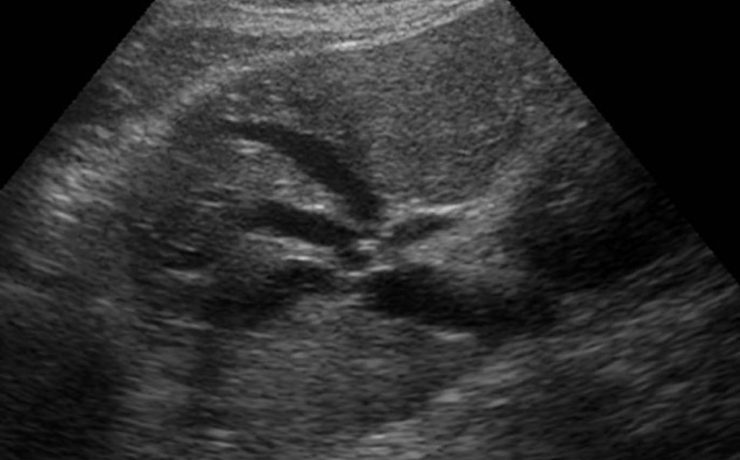

Fibroadenoma de tejido mamario ectópico axilar

Es el tumor benigno más común de la glándula mamaria de mujeres jóvenes. A pesar de que un 95% de las mujeres existe tejido mamario en la axila (cola de mama) y de que incluso en 6 de cada 100 es clínicamente evidente. Los reportes de este tumor en la